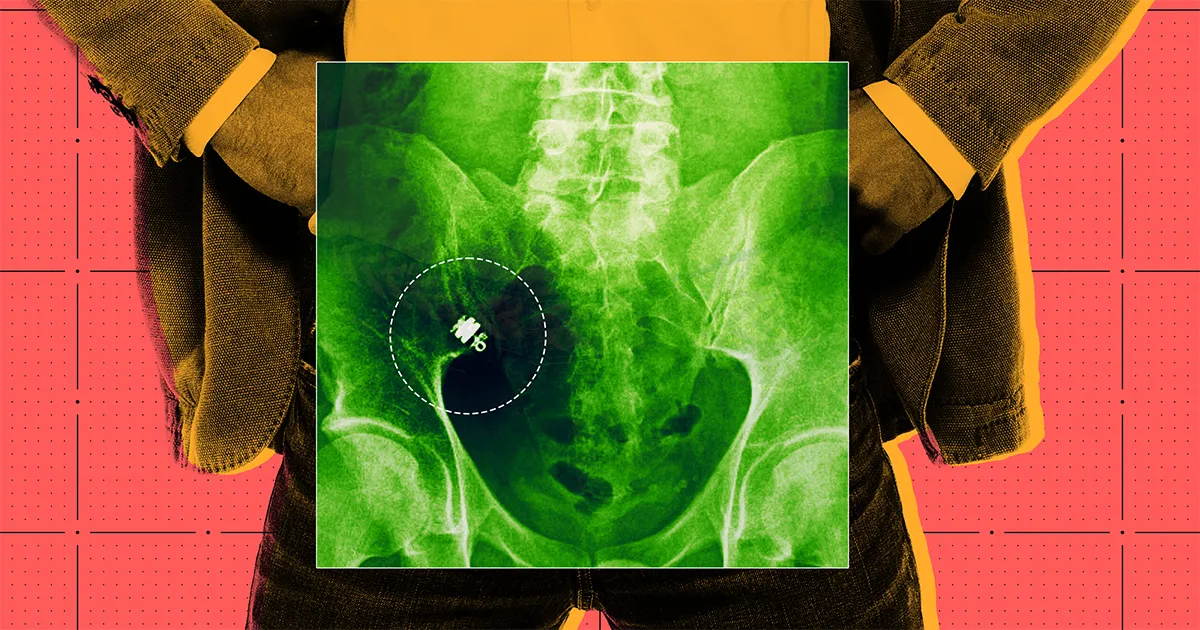

Face à la frustration grandissante et sans diagnostic clair, Thiessen et son gastro-entérologue ont décidé d’utiliser une méthode plus novatrice : une caméra capsule appelée PillCam, développée par Medtronic. Cette petite caméra sans fil, ressemblant à un gros comprimé, était destinée à être avalée pour explorer le système gastro-intestinal.

En juillet 2024, après avoir avalé la caméra, Thiessen a attendu le passage de celle-ci à travers son corps, mais les jours ont passé sans qu’il n’aperçoive cette dernière. Il a d’abord pensé qu’il l’avait simplement manquée puis, après deux semaines, un radio a confirmé qu’elle était toujours à l’intérieur de lui.

Bien que les complications puissent survenir avec ces dispositifs, on les considère généralement comme sûres. Dans le cas de Thiessen, il a reçu un traitement à base de stéroïdes pour tenter de libérer la caméra, puis divers examens ont révélé que celle-ci était coincée dans une zone difficile d’accès de son intestin. Faute de pouvoir y parvenir par endoscopie, il a fallu envisager une résection intestinale, une intervention chirurgicale majeure.